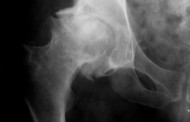

Подагрой называют патологический процесс в суставном аппарате хронического характера. Основным проявлением является выраженный болевой синдром. Лечение проводится консервативными либо хирургическими методами. Это позволит улучшить качество жизни человека, его подвижность. Лечение можно осуществлять амбулаторно, только при этом нужно соблюдать все рекомендации лечащего врача.

Развитие болезни характеризуется острым началом. Его признаки зачастую проявляются в период сна человека. В начале отложение солей мочевой кислоты происходит в крупных суставах фаланг пальцев, коленей, стоп. Обычно клиническая картина заболевания ярко выражена, поэтому поставить правильный диагноз не составляет труда.

Если не придерживаться правильного питания, патологический процесс распространяется на иные сочленения. Высокая дозировка урата натрия отмечается не только в самих суставах, но и в хрящевых и связочных структурах.